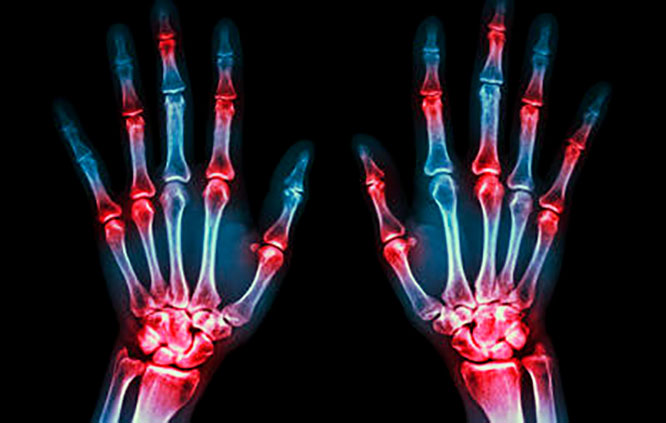

Боли в суставах – одна из жалоб любого современного человека. Не всегда за ней скрыто обычное физическое переутомление. Это может быть и тяжелая патология опорно-двигательной системы, что диктует необходимость обязательного выяснения точной причины возникновения боли. Но, как показывает практика, в силу постоянного дефицита времени умеренно выраженные симптомы длительное время остаются без должного внимания.

Среди обезболивающих средств, которые показаны от боли в суставах, выделяют препараты, предназначенные исключительно для симптоматического лечения и патогенетической терапии. В первом случае действие средства направлено лишь на купирование болевого синдрома, во втором, кроме обезболивания, отмечается влияние на механизмы запуска и прогрессирования болезни.

Поэтому борьба с длительно сохраняющимися мучительными болями в суставах должна быть дифференцированной и основываться на причине их возникновения.